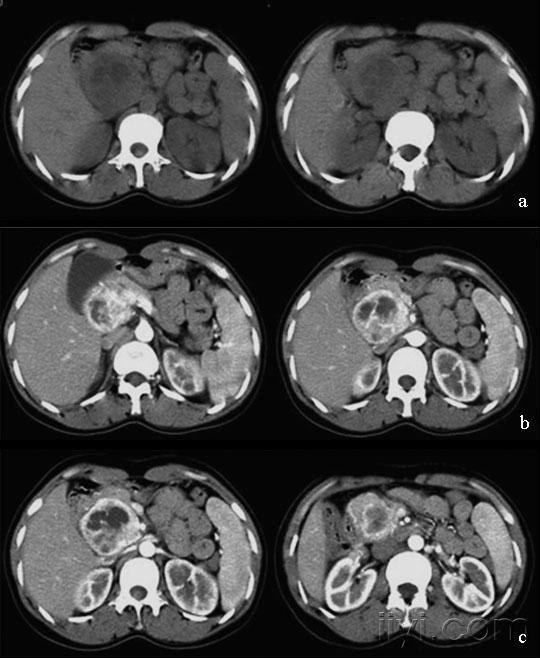

胰岛细胞瘤影像学表现

图片尺寸635x859